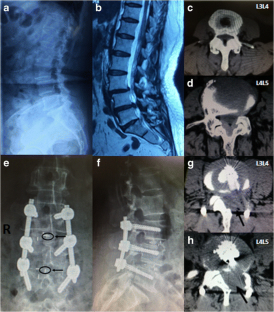

Fig. 2